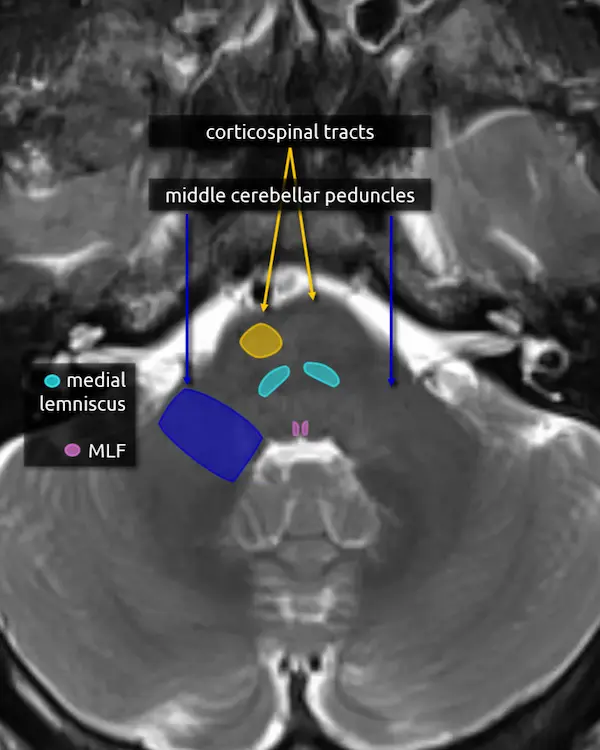

3. Middle cerebellar peduncles:

The middle cerebellar peduncles are the largest of the cerebellar peduncles and connect the cerebellum to the pons. The fibers are entirely afferent, originating from contralateral pontine nuclei and terminating in the cerebellum. Over 90% of the fibers in the middle cerebellar peduncles belong to the corticopontocerebellar pathway (see below).

There are many causes of middle cerebellar peduncle signal abnormality, usually resulting from conditions that can cause white matter edema, degeneration, or gliosis. Bilateral T2 hyperintensity of the middle cerebellar peduncles is a classic but not specific sign of fragile X-associated tremor/ataxia syndrome (FXTAS). Multiple system atrophy cerebellar type (MSA-C) and spinocerebellar ataxia are other classic causes of middle cerebellar peduncle atrophy and signal abnormalities.

3. Corticospinal tracts

The corticospinal, corticobulbar, and corticopontocerebellar tracts continue inferiorly from the cerebral peduncles.

Lesions of the corticospinal tracts will cause motor deficits of the body and limbs. Sparing or involvement of the corticospinal tracts is a characteristic finding of several conditions, e.g., sparing of the corticospinal tracts is responsible for the "trident sign" of osmotic demyelination syndrome. The corticobulbar tract is located along the medial aspect and can be selectively damaged at this level, producing facial weakness.

5. Medial lemniscus

The medial lemniscus is an ascending sensory pathway that spans the entire brainstem, originating at the nucleus gracilis and cuneatus (see level 5) in the medulla and ending at the primary sensory nucleus of the thalamus: the ventral posterolateral nucleus (VPL). It begins medially in the medulla and becomes more lateral at the level of the midbrain, located in close proximity to the substantia nigra. It is responsible for vibration sensation, fine touch, and proprioception.

Lesions involving the medial lemniscus may cause contralateral loss of vibration sensation and joint position sensation on physical exam with symptoms of numbness and paresthesias.

6. Medial longitudinal fasciculus (MLF)

The MLF is an ascending and descending pathway responsible for coordinating eye movements. It connects all of the cranial nerve nuclei that innervate the extraocular muscles (CN III, IV, and VI) as well as the vestibulocochlear nuclei (CN VIII). The MLF spans the entire brainstem, however lesions producing visual symptoms will probably be in the midbrain or pons.

There are characteristic syndromes that result from damage to the MLF, most commonly internuclear ophthalmoplegia (INO) or INO-plus syndromes. A common clinical scenario is a patient with multiple sclerosis who develops a demyelinating lesion along the MLF in the midbrain or pons and presents with bilateral INO.